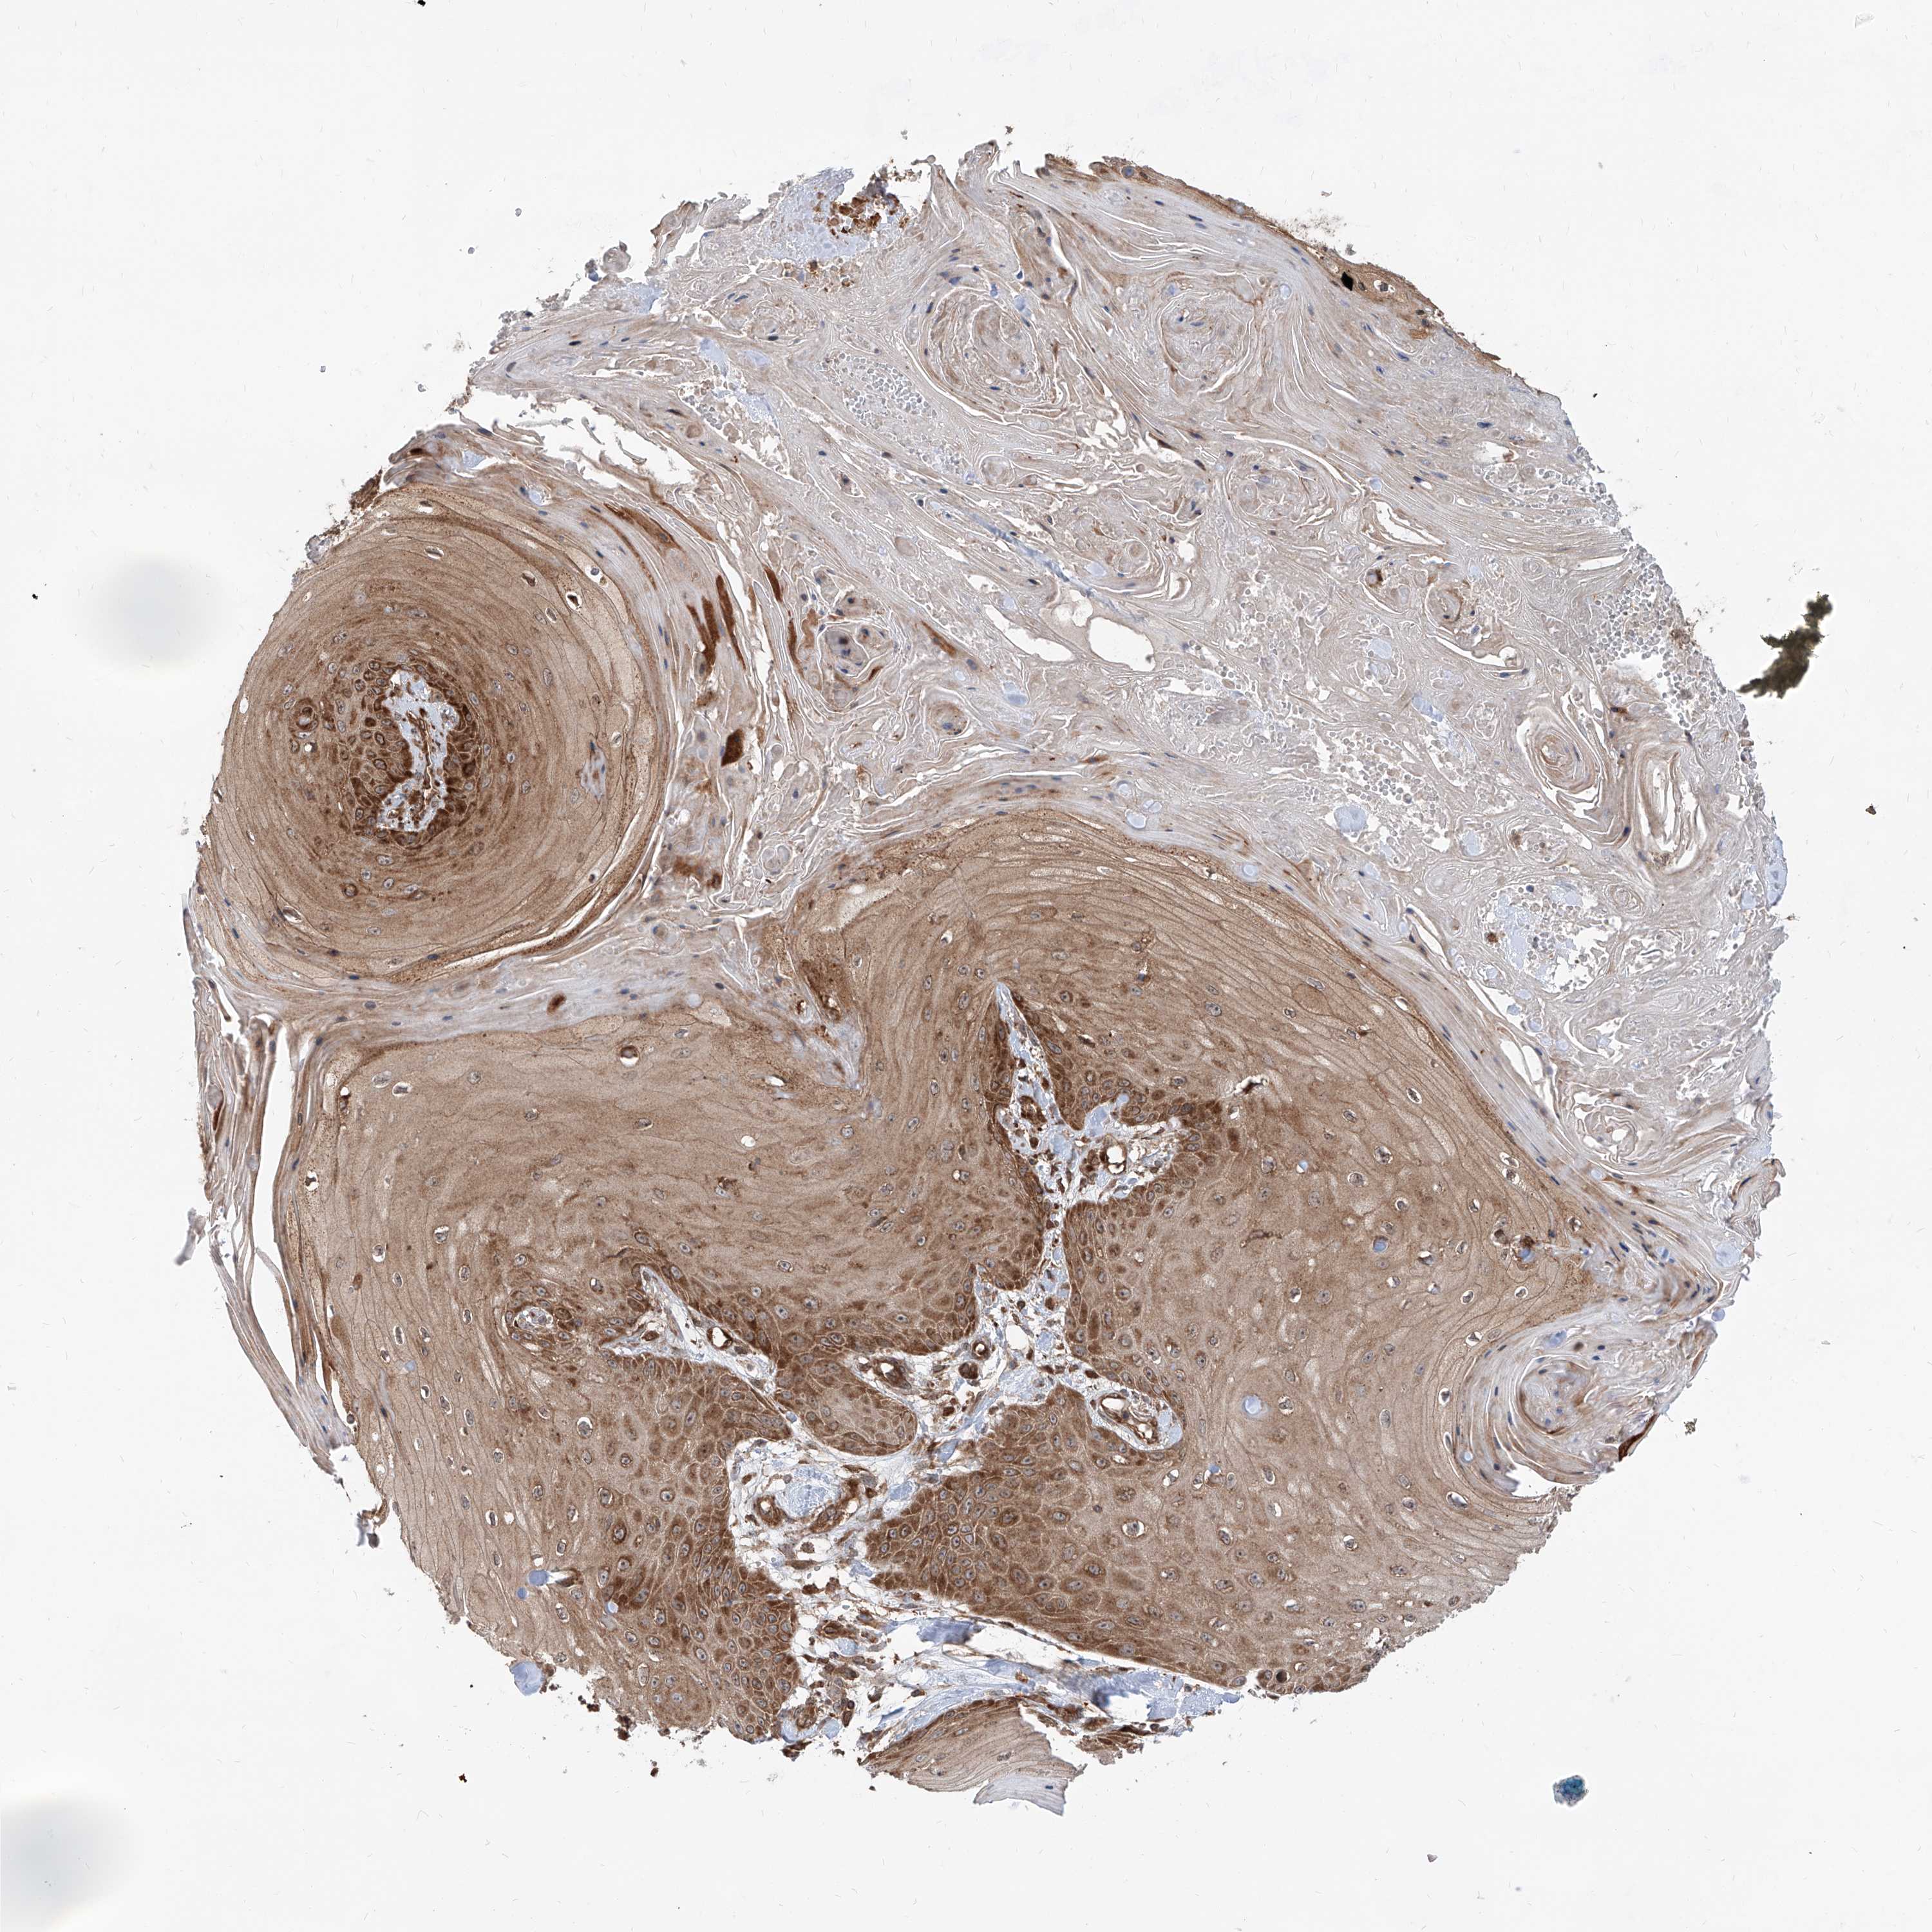

Basal cell and squamous cell cancer

SKIN CANCER - Protein expressioni

A mouse-over function shows sample information and annotation data. Click on an image to view it in a full screen mode. Samples can be filtered based on level of antibody staining by selecting one or several of the following categories: high, medium, low and not detected. The assay and annotation is described here.

Each image is clickable and will lead to virtual microscopy that enables deeper exploration of all samples and also displays staining intensity scores, fraction scores and subcellular localization as well as patient and tissue information for each sample.

Antibody HPA031572

Antibody HPA031573

Squamous cell carcinoma, NOS

Squamous cell carcinoma, metastatic, NOS